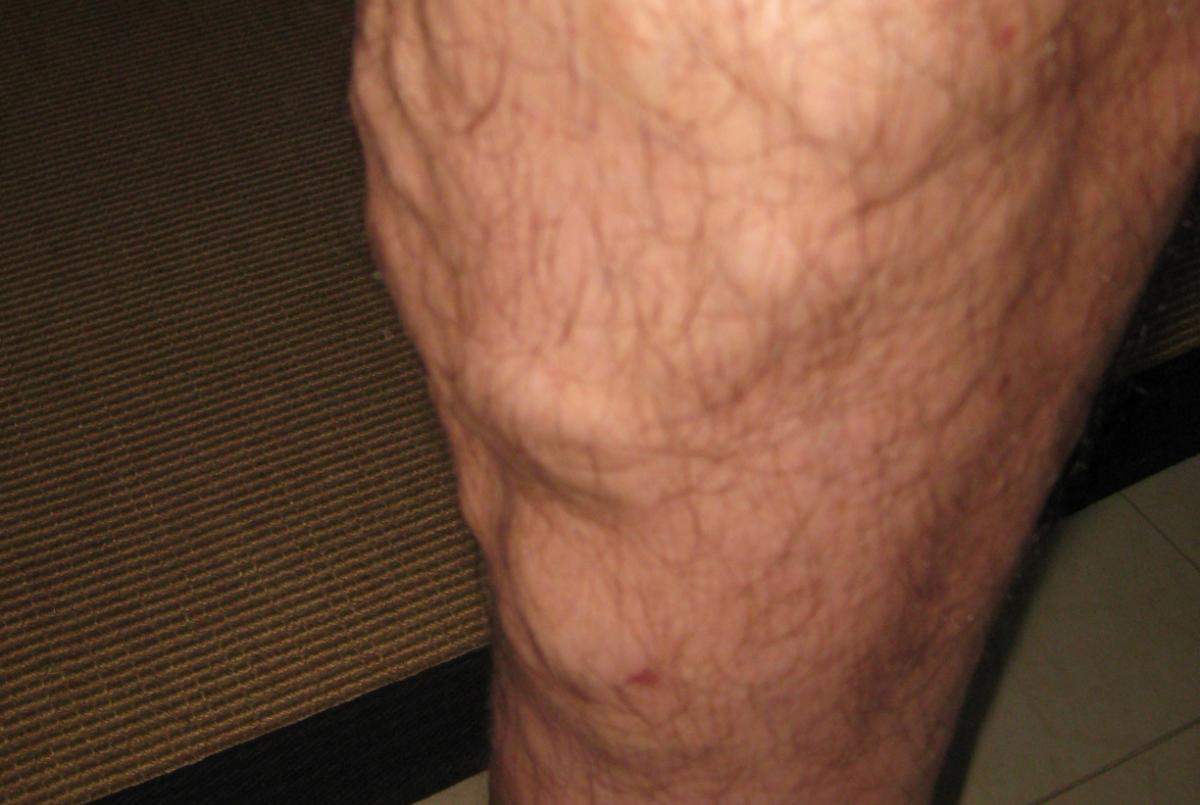

24. All In Vein

Had a 911 call with a hysterical patient. Lights and sirens to the address.

"Ma'am, you aren't dying. You have varicose veins."